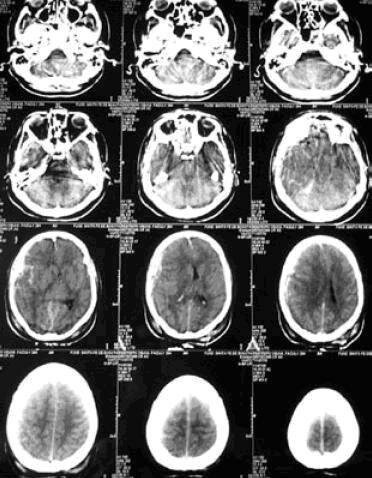

Caracterizado por el surgimiento de nuevas tecnologías técnicas de investigación no invasivas como las tomografías y resonancias magnéticas que ayudan a visualizar el funcionamiento del cerebro mientras los pacientes están realizando diversas actividades y así identificar con mayor precisión las áreas asociadas con funciones específicas, igualmente está el surgimiento de métodos de rehabilitación para pacientes con alteraciones cognoscitivas y finalmente el aumento en publicaciones.

• La incorporación y difusión de las técnicas imagenológicas contemporáneas, en especial la escanografía cerebral o la tomografía axial computarizada (TAC).

La incorporación y difusión de las técnicas imagenológicas contemporáneas, en especial la escanografía cerebral o la tomografía axial computarizada (TAC).